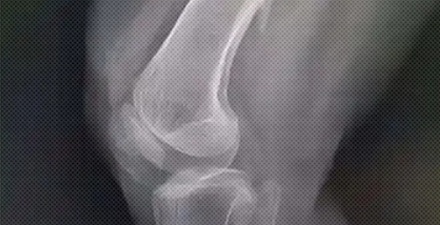

为什么医生会让骨折的病人等几天再手术?

得等伤口消肿,要不然手术的风险太高。

骨折后,伤口的肌肉等软组织会充血水肿。这时候手术,里面的肉往外鼓,伤口很难缝上。

就算硬是给缝上了,刀口两边的皮肤还可能会缺血坏死、切口崩开,甚至导致钢板外露。

另外,伤口周围的组织抵抗力也很差。

要是马上动手术,特别容易让细菌钻空子。旦感染引发骨髓炎,那可比骨折遭罪多了。